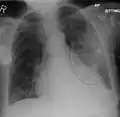

AP CXR showing left lower lobe pneumonia associated with a small left sided pleural effusion

AP CXR showing right lower lobe pneumonia

AP CXR showing pneumonia of the lingula of the left lung

Left upper lobe pneumonia with a small pleural effusion.